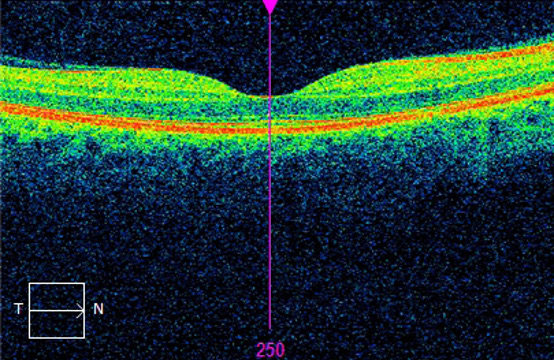

Macula – The central, indented part of the retina where light rays, ideally, come to a focal point. It is 100 times more sensitive that the other parts of the retina to allow clear vision of detailed objects.